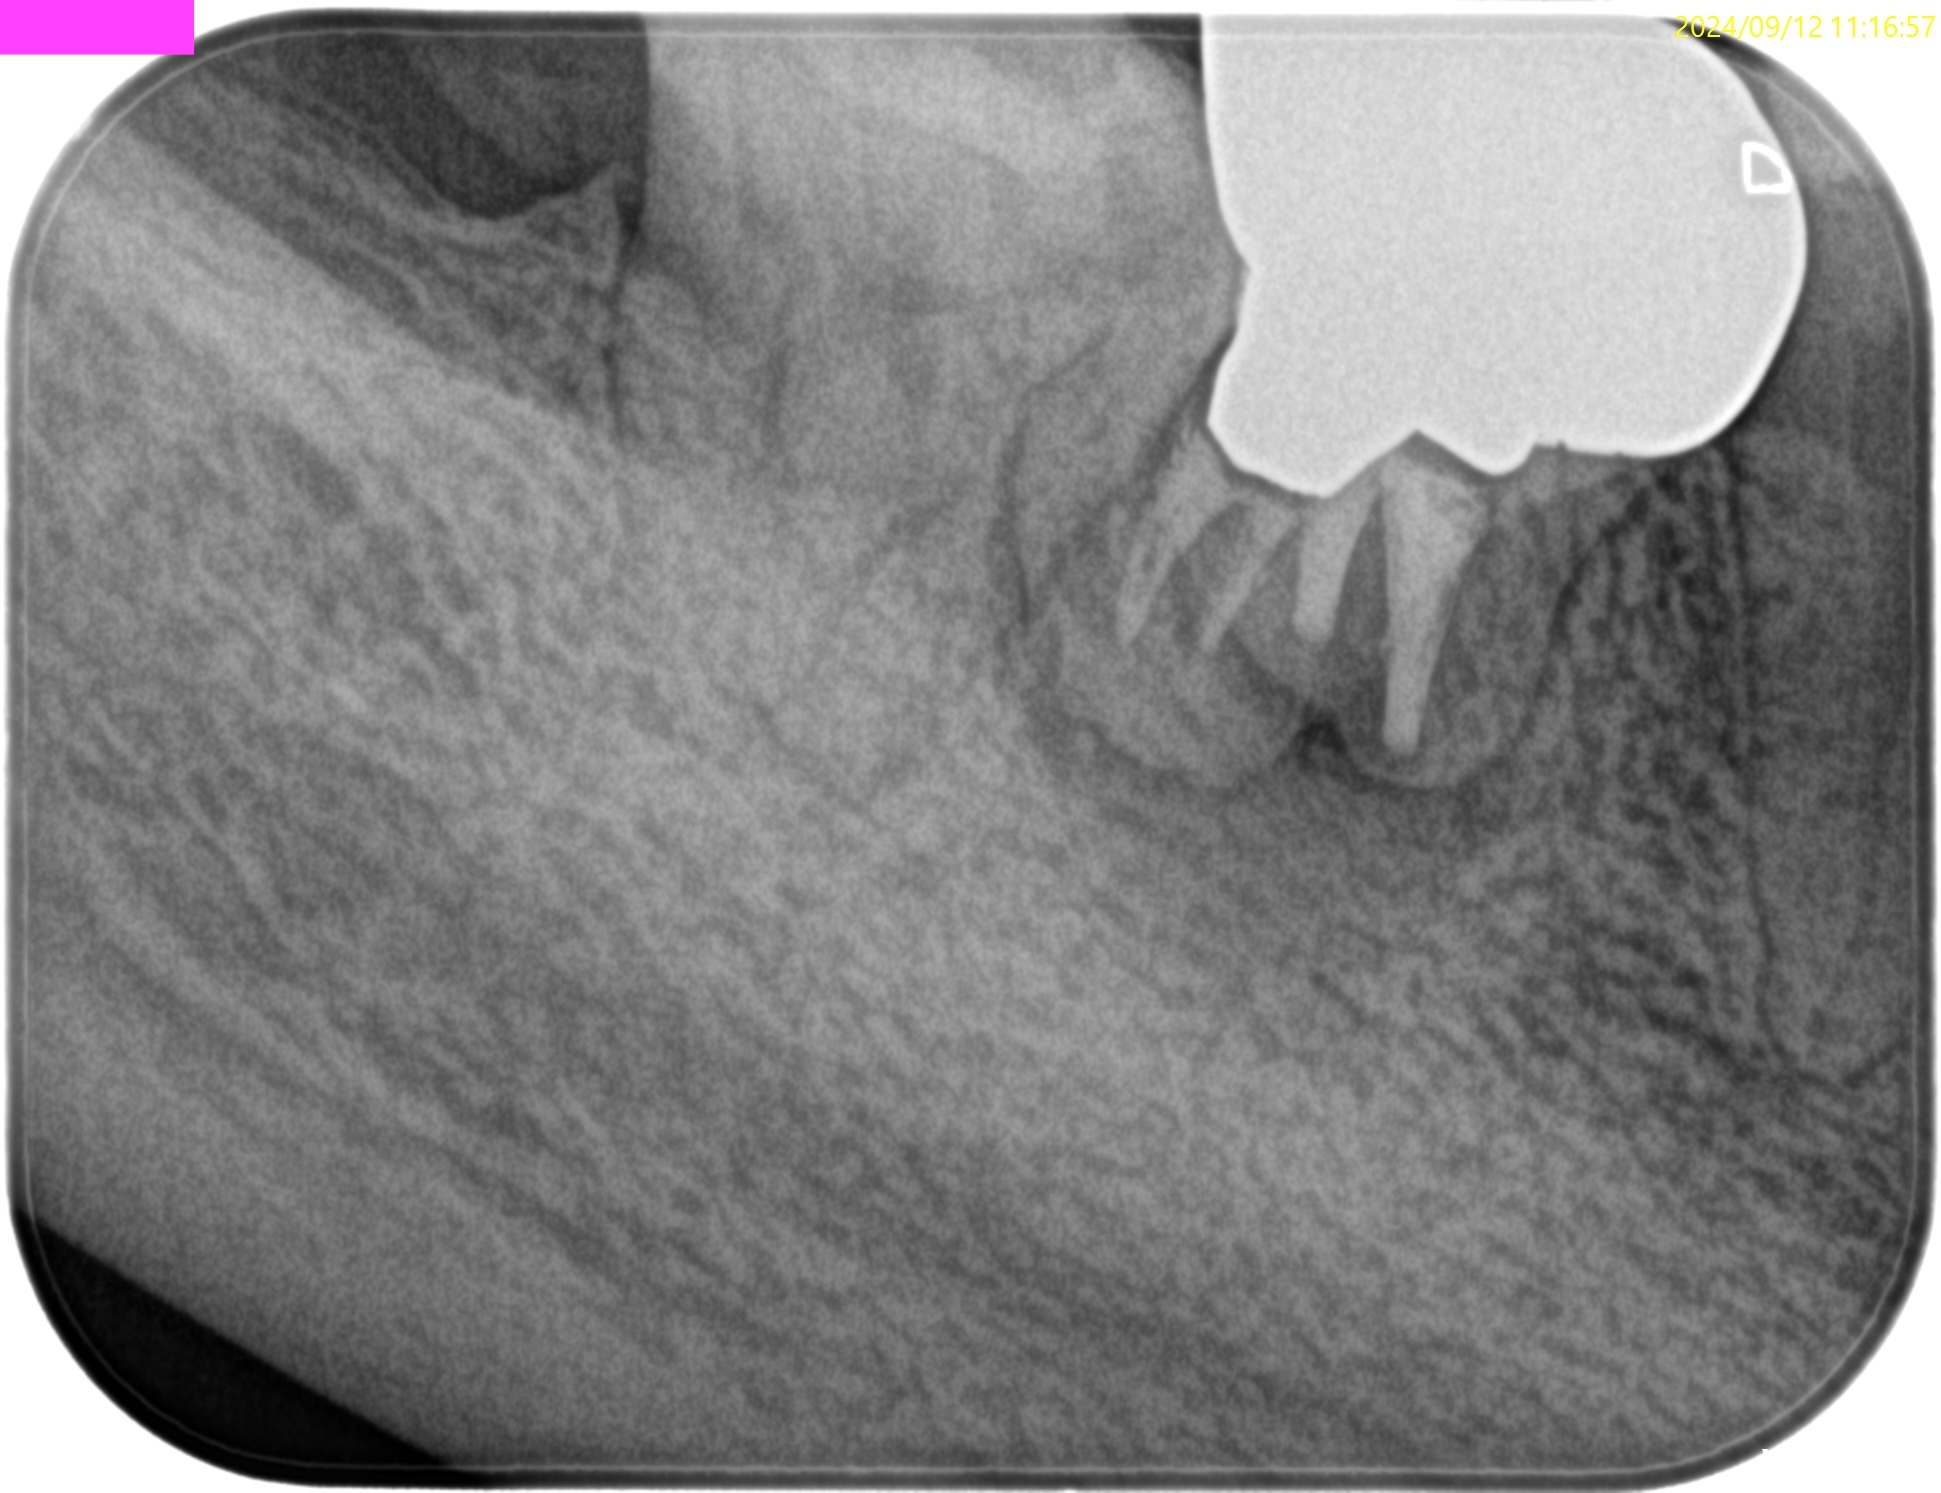

PA(2024.9.12)

Pre-op Endo test(2024.9.12)

頬側と舌側の2箇所にSinus tractがあった。

この時点で外科が決定的だ。